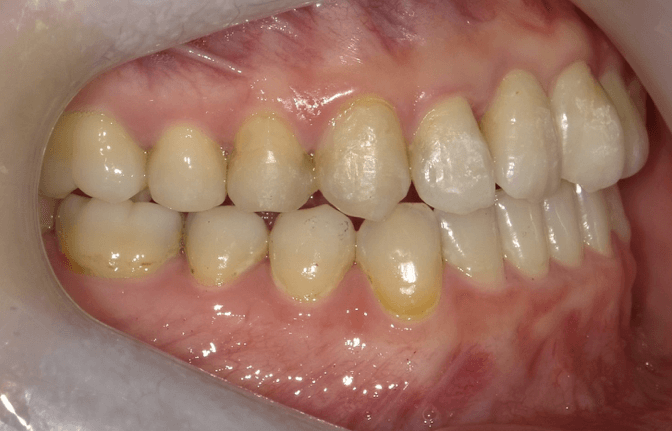

叢生(中等度)

BEFORE

AFTER

担当医コメント

上下の中等度の叢生がある。上顎の大臼歯の遠心移動が出来るスペースがある、補綴が多いのでIPRによってスペースが確保出来るのでインビザラインで治療を行った。

治療の概要

年齢/性別

26歳 女性

主訴

上下の歯並びが気になる。八重歯が気になるでした。

リスク

歯肉退縮が起こる可能性がある。叢生の改善により、ブラックトライアングルが出て来る可能性がある。

費用

85万円(矯正費用)

術前

術中

術後